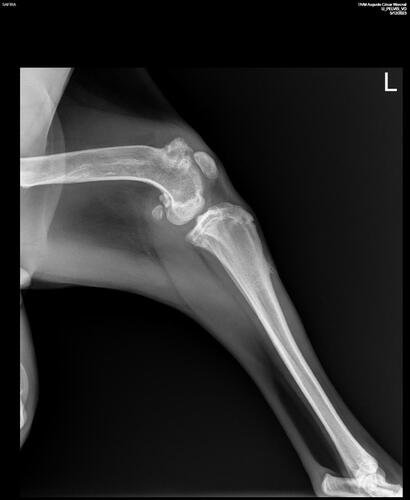

Como era filhote, Safira cresceu com a perna quebrada, fazendo com que o seu osso calcificasse da maneira errada, implicando diretamente no encurtamento da sua perna traseira. Além da perna quebrada, foi descoberto também que Safira possui um "corpo estranho", possível tumor, na mesma perna.

Esse será o primeiro passo do tratamento. Safira ainda vai passar por uma cirurgia ortopédica para tratar da perna quebrada, porém não temos ainda um orçamento, visto que é necessário os primeiros cuidados (procedimentos citados acima).